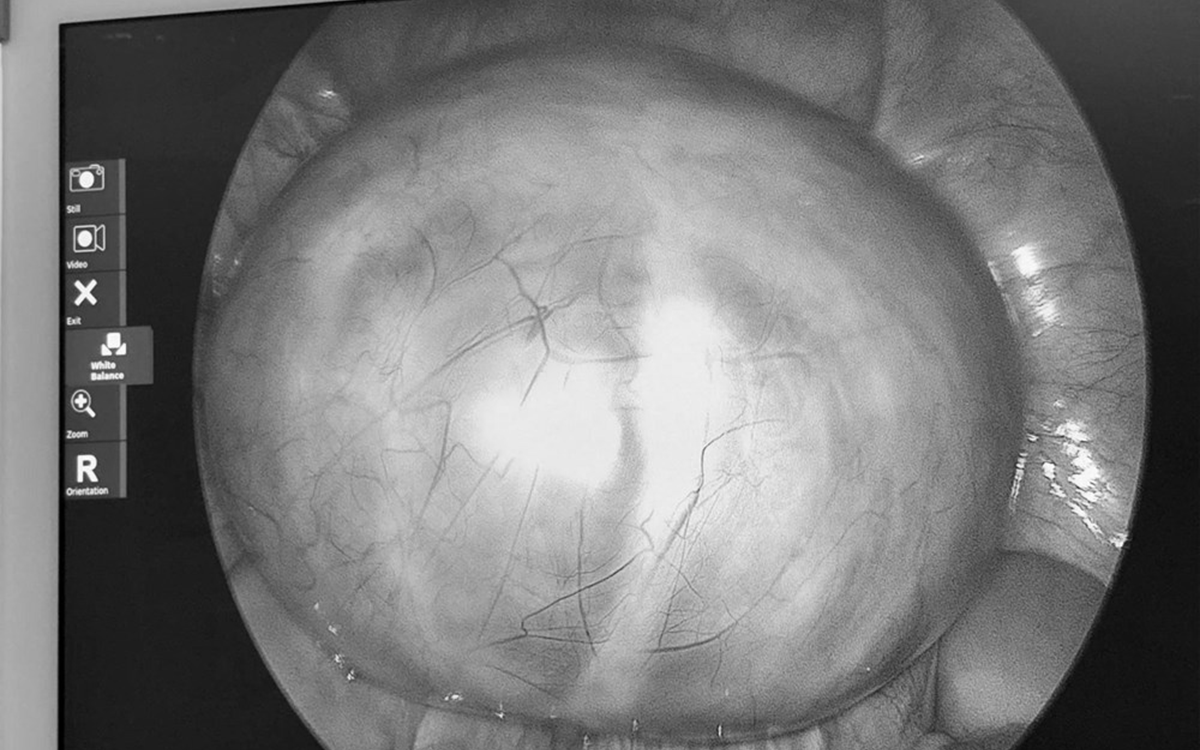

Khối u buồng trứng khổng lồ ở bệnh nhi. Ảnh BVCC.

Khi nhập viện, bác sĩ ghi nhận bụng bệnh nhi mềm, xuất hiện khối vùng hạ vị phát triển vượt qua rốn, ấn không đau. Các xét nghiệm dấu ấn khối u như AFP và beta-hCG đều trong giới hạn bình thường. Tuy nhiên, siêu âm và chụp CT cho thấy, một khối u ổ bụng rất lớn, kích thước khoảng 18-25cm, cấu trúc hỗn hợp gồm dịch và mô đặc. Bên trong khối u có vách, vùng mô đặc, vôi hóa và mô mỡ, gợi ý khối u xuất phát từ buồng trứng phải. Khối u còn chèn ép niệu quản phải, gây giãn niệu quản và thận phải ứ nước.

Theo BS.CKI Nguyễn Hiền (Khoa Ngoại Tổng hợp, Bệnh viện Nhi đồng 2), khi tiến hành phẫu thuật, các bác sĩ ghi nhận khối u có kích thước khoảng 20x25x10cm, nặng gần 4kg, chiếm gần toàn bộ buồng trứng phải. Do khối u lớn, có thành phần mô đặc và nguy cơ ác tính, ê-kíp quyết định cắt trọn buồng trứng phải cùng vòi trứng phải nhằm loại bỏ hoàn toàn tổn thương. Ca phẫu thuật diễn ra thuận lợi, bệnh nhi hồi phục tốt sau mổ.